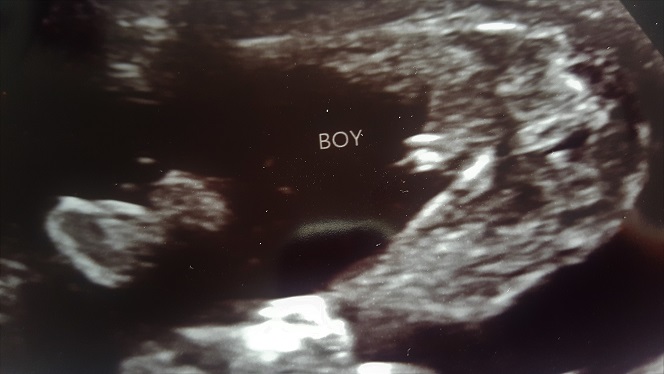

Is this a boy at 16 weeks? We didn't have long in the scan and the tech said that she wanted to go back and check but never did...x

Looks like a boy. Congrats!

Thank you, that will be boy number 3 then :3kids: xxx